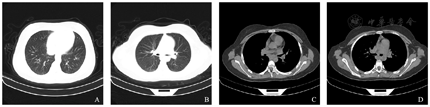

入院后暂给予抗感染、雾化吸入及双嘧达莫对症治疗,因患儿腹胀明显,且饮食欠佳,伴反酸,偶有胸骨后疼痛,于2021年9月10日完善电子胃镜显示:下段近贲门、胃体、胃窦可见糜烂灶;胃底黏膜可见少量胆汁附着。胃镜下组织活检结果:(1)食管:组织表面被覆鳞状上皮,局灶鳞状上皮轻度不典型增生,组织充血、水肿,淋巴细胞、浆细胞、大量嗜酸性粒细胞浸润;免疫组织化学结果:CK5/6[1+],ki67[上皮下1/3+,间质5%],p53[-],CD15[约400个/HPF]。(2)胃窦:黏膜腺上皮未见明显异常,固有膜内见较多嗜酸性粒细胞浸润,约200个/HPF。(3)十二指肠降部:黏膜腺上皮未见明显异常,固有膜内见淋巴细胞、浆细胞及较多嗜酸性粒细胞浸润,约100个/HPF(图3)。综合上述临床表现、实验室、组织病理及影像学检查,经多学科会诊后诊断为IHES。给予患儿口服泼尼松[1 mg/(kg·d),50 mg]治疗3 d后,复查血常规:白细胞计数10.94×109/L,嗜酸性粒细胞百分比7.3%,嗜酸性粒细胞计数0.80×109/L,血小板计数345×109/L。应用激素治疗1周后患儿未再发热,胸闷、腹胀、尿痛明显减轻,复查血常规:白细胞计数12.47×109/L,嗜酸性粒细胞百分比2.1%,嗜酸性粒细胞计数0.26×109/L,血小板计数397×109/L。凝血功能:FDP 4.88 μg/mL,D-二聚体1.21 μg/mL。复查心包积液及胸腹超声提示心包积液微量,未见胸水,腹水较前明显减少,遂出院随诊。

食管、胃窦、十二指肠降部固有膜内大量嗜酸性粒细胞浸润。